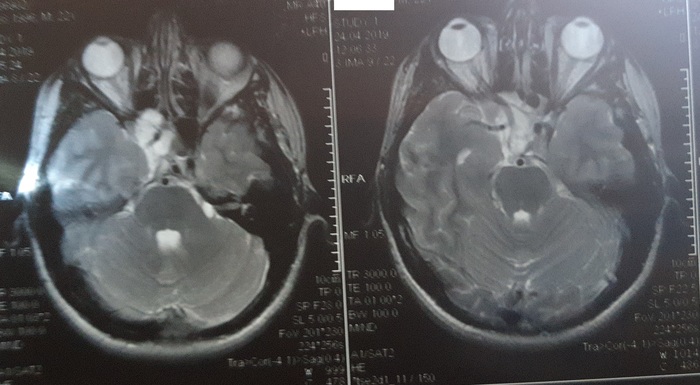

На этот раз мне дали диск. Постарался найти те же снимки, которые выложил в прошлый раз. Вот картинки:

Хорошие новости, опухоль в половину стала меньше. Нейрохирург пояснил, что опухоль была как пробка, вот и полилось. Попросил оставить доки, чтобы с коллегами посовещаться в другой день, а то уже конец рабочего для был.